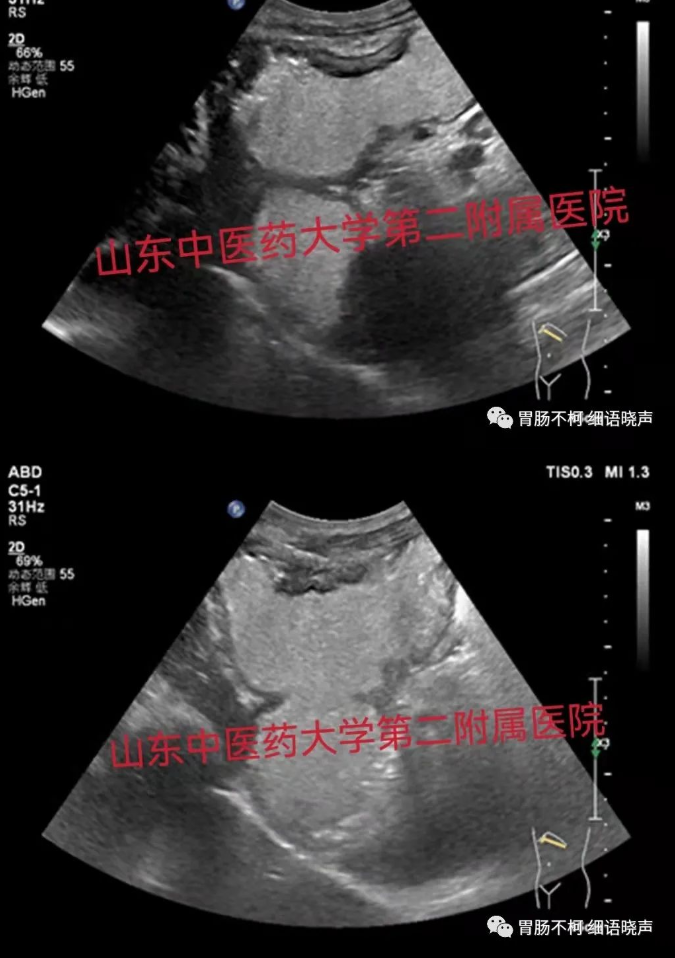

病例二,胃角处胃壁增厚性病变,层次不清晰,回声偏低:

病例三,胃体偏后壁胃壁增厚性病变,层次尚清晰,黏膜面浅溃疡形成: